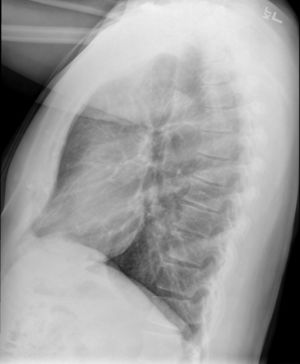

Causes include breathing in toxic fumes, respiratory infections, connective tissue disorder or complications following a bone marrow or heart-lung transplant.[1] Symptoms may not occur until two to eight weeks following toxic exposure or infection.[1] The underlying mechanism involves inflammation that results in scar tissue formation.[1] Diagnosis is by CT scan, pulmonary function tests or lung biopsy.[1] A chest X-ray is often normal.[4]

Medical imaging

Early in the disease chest radiography is typically normal but may show hyperinflation.[6] As the disease progresses a reticular pattern with thickening of airway walls may be present.[4][6] HRCT can also show air trapping when the person being scanned breathes out completely; it can also show thickening in the airway and haziness in the lungs.[11] A common finding on HRCT is patchy areas of decreased lung density, signifying reduced vascular caliber and air trapping.[6] This pattern is often described as a "mosaic pattern", and may indicate obliterative bronchiolitis.[6]